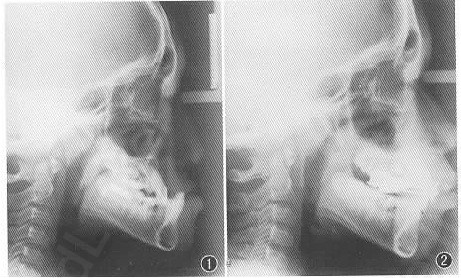

12岁男性,地包天求治

上颌骨严重发育不足

上颌发育不足。 采用颅骨外固定牵引装置,施牵引成骨术。